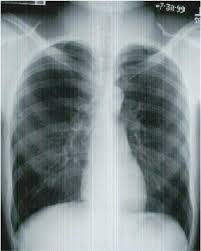

Chest Radiograph